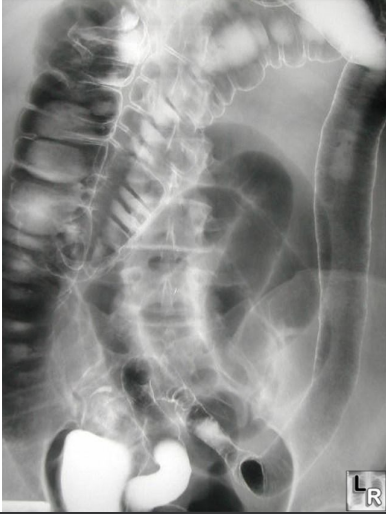

Q

UC may be identified on imaging with _ sign

A

UC may be identified on imaging with lead pipe sign

Crohn's disease is associated with _ sign on X-ray

Crohn's disease is associated with **string sign** on X-ray (ileum)